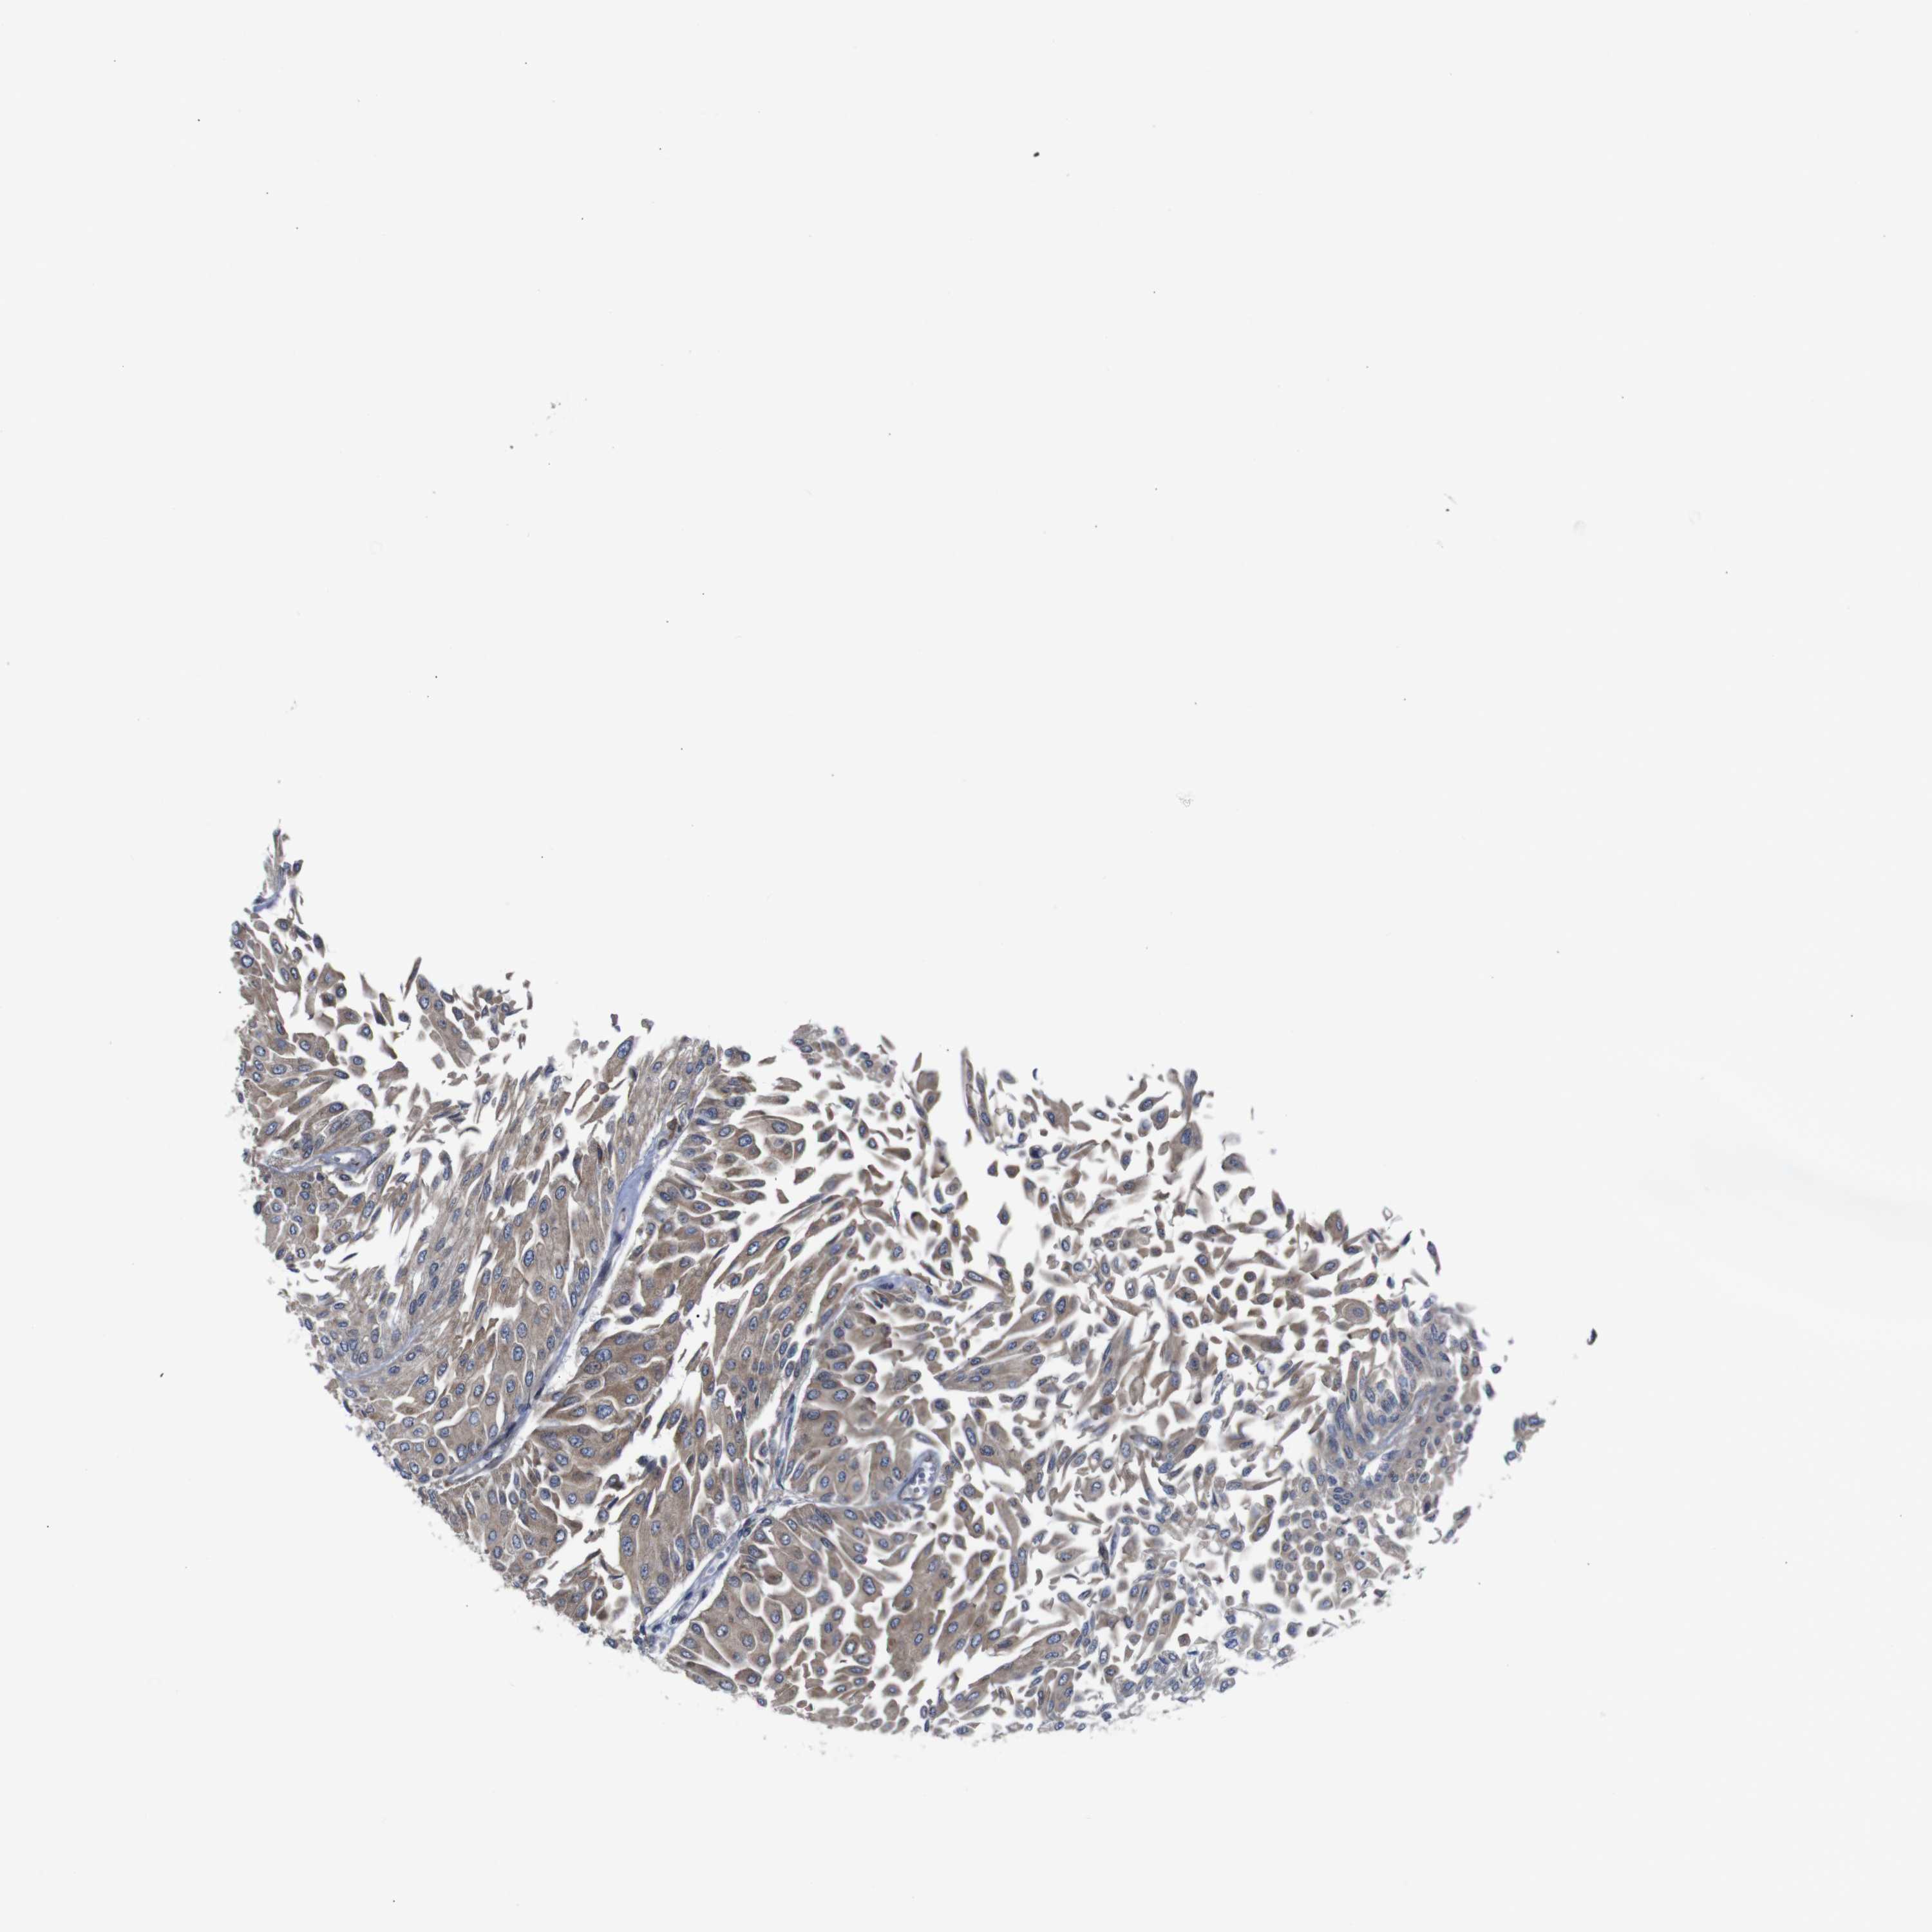

UROTHELIAL CANCER - Protein expressioni

A mouse-over function shows sample information and annotation data. Click on an image to view it in a full screen mode. Samples can be filtered based on level of antibody staining by selecting one or several of the following categories: high, medium, low and not detected. The assay and annotation is described here.

Note that samples used for immunohistochemistry by the Human Protein Atlas do not correspond to samples in the TCGA dataset.

Antibody stainingi

Antibody staining in the annotated cell types in the current human tissue is reported as not detected, low, medium, or high, based on conventional immunohistochemistry profiling in selected tissues. This score is based on the combination of the staining intensity and fraction of stained cells.

Each image is clickable and will lead to virtual microscopy that enables deeper exploration of all samples and also displays staining intensity scores, fraction scores and subcellular localization as well as patient and tissue information for each sample.

Antibody HPA012542

Antibody CAB009329

Antibody CAB015217

Staining

High

Medium

Low

Not detected

Intensity

Strong

Moderate

Weak

Negative

Quantity

>75%

75%-25%

<25%

None

Location

Nuclear

Cytoplasmic/membranous

Cytoplasmic/membranous,nuclear

Urothelial carcinoma, Low grade

Urothelial carcinoma, High grade